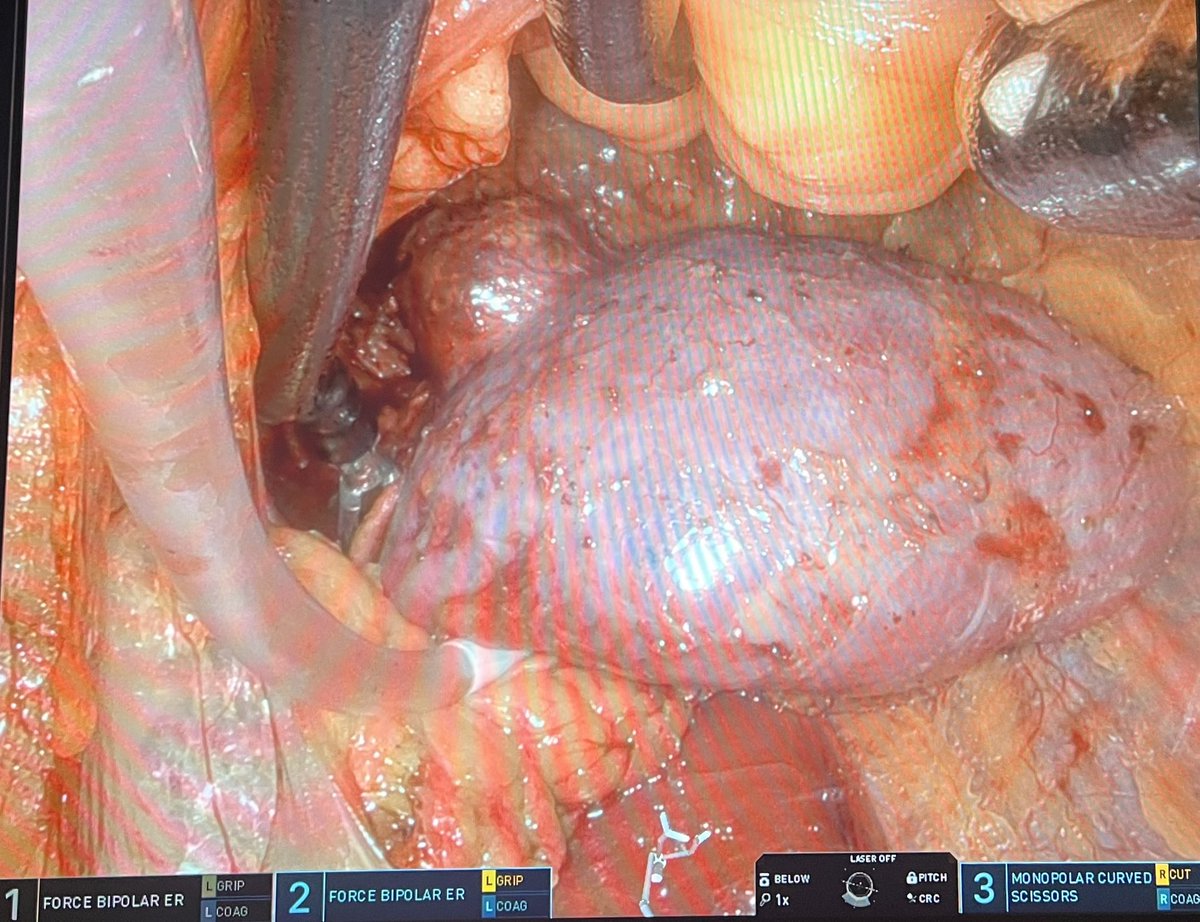

Great presentation by @RyanNelson762 demonstrating how to control bleeding calmly and identifying important studies which highlight the safety of SP partial nephrectomy compared with MP but do confer slightly longer ischemic times. @Endo_Society @SocietySURS @uretericbud